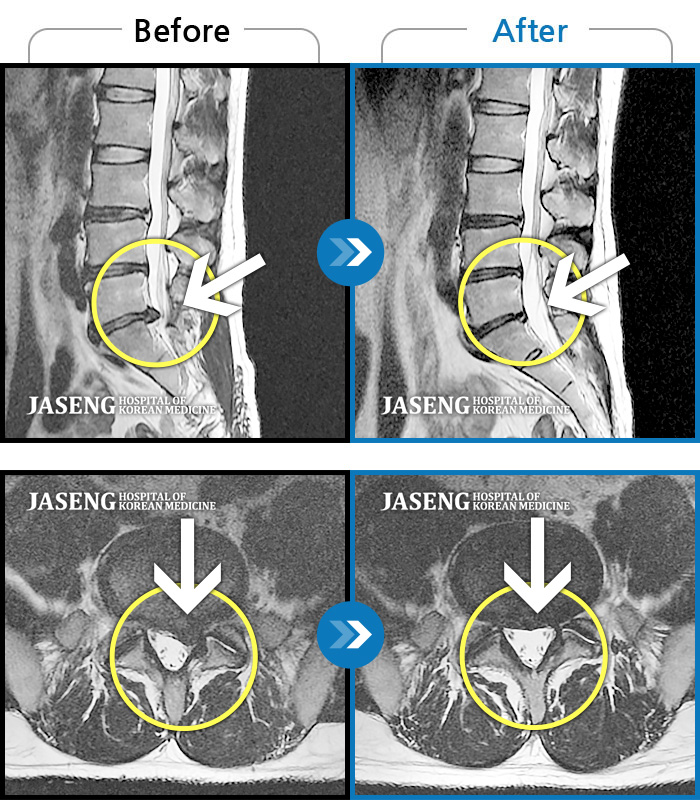

Before

After

환자에게 사전 동의를 받아 동일 조건에서 촬영되었습니다.

개인에 따라 치료 후 부작용이 발생할 수 있으니 의료진과 상담 후 치료를 진행하시기 바랍니다.

처음 내원시 심한 허리 통증과 오른쪽 엉덩이부터 허벅지 종아리까지 저리고 당기는 증상을 호소하셨습니다.